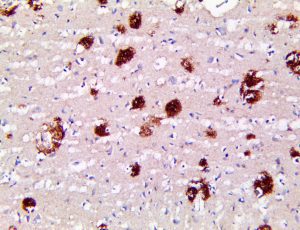

It is the ICU physician who is most likely to witness one of the deadliest manifestations of the abnormal immunological response, the cytokine storm syndrome (CSS). This response is also referred to by some as the cytokine release syndrome (CRS). CSS is characterized by continuous activation and expansion of macrophage and lymphocyte populations, which secrete large amounts of cytokines, causing the cytokine storm. This massive cytokine release is akin to hemophagocytic lymphohistiocytosis (HLH) disease, a syndrome characterized by initial unchecked and persistent activation of cytotoxic T lymphocytes and NK cells.

Clinical and laboratory manifestations of HLH include fever, enlarged liver and/or spleen, neurologic dysfunction, coagulopathy, liver dysfunction, cytopenias (i.e., low levels of erythrocytes, leukocytes, and/or platelets), hypertriglyceridemia, hyperferritinemia, hemophagocytosis, and eventually diminished NK cell activity as the immune system becomes progressively paralyzed. HLH can be familial (primary HLH) or secondary to another disease process (sHLH), such as rheumatic disease, in which it is referred to as macrophage activation syndrome (MAS, characterized by elevated ferritin).